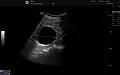

Renal ultrasonography of a simple renal cyst with posterior enhancement.

Renal cyst as seen on abdominal ultrasound